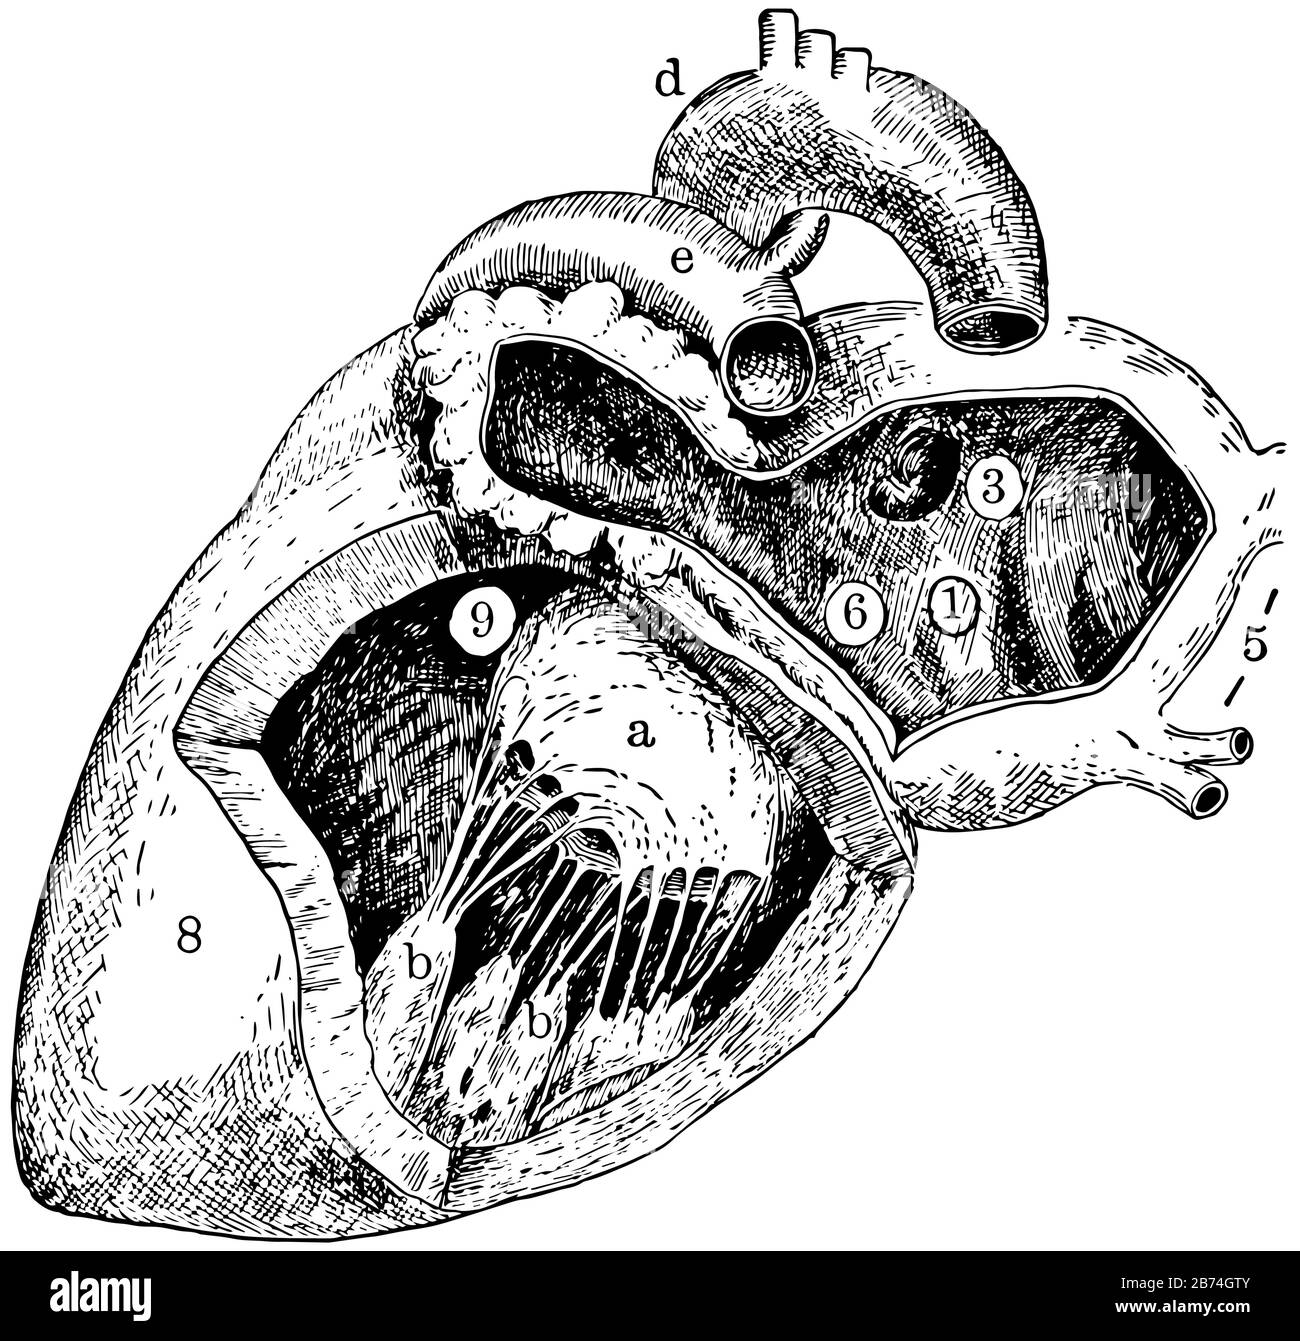

This diagram represents Left Side of Heart, vintage line drawing or engraving illustration. Stock Vectorhttps://www.alamy.com/image-license-details/?v=1https://www.alamy.com/this-diagram-represents-left-side-of-heart-vintage-line-drawing-or-engraving-illustration-image348611003.html

This diagram represents Left Side of Heart, vintage line drawing or engraving illustration. Stock Vectorhttps://www.alamy.com/image-license-details/?v=1https://www.alamy.com/this-diagram-represents-left-side-of-heart-vintage-line-drawing-or-engraving-illustration-image348611003.htmlRF2B74GTY–This diagram represents Left Side of Heart, vintage line drawing or engraving illustration.